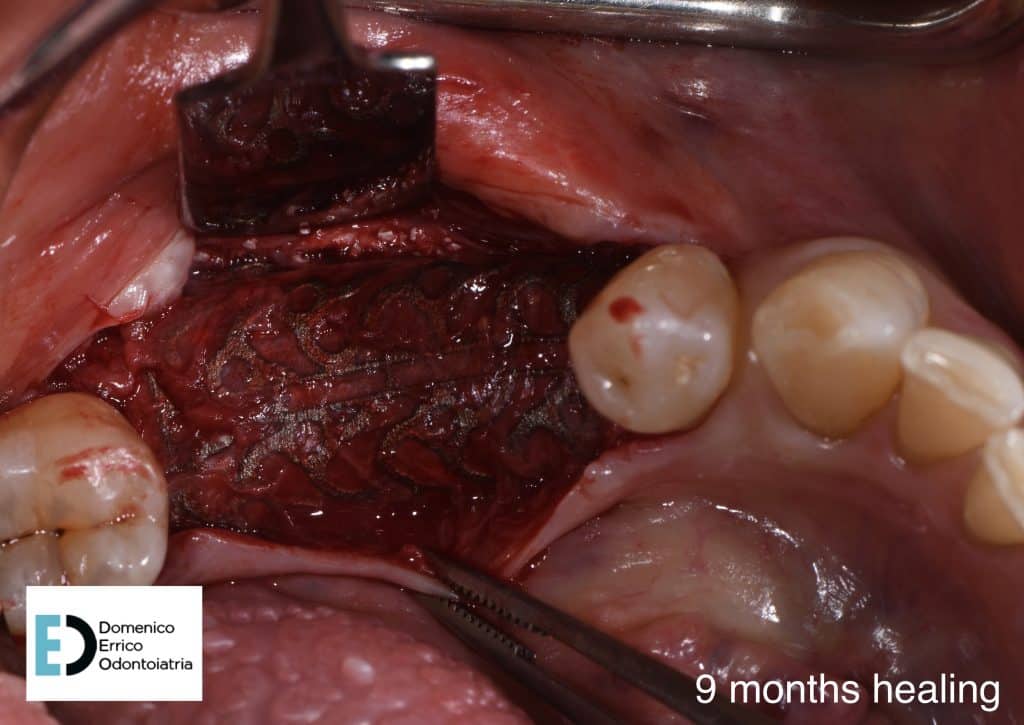

The treatment objectives are primarily functional: the restoration of volumes, necessary for implant rehabilitation due to insufficient bone height for fixture placement applying a mesh with a filler, consisting of 50% autologous bone and 50% heterologous bone; the reinstatement of chewing function by a second intervention to remove the mesh and simultaneously place two implant fixtures, concurrent with an increase of adherent gingival tissue level; and finally, the goal is to achieve the correct vertical relationship between the upper and lower arches through prosthetic rehabilitation of the upper arch with the replacement of the old prosthetic device.

After 4 months we can appreciate the perfect tissues healing, the bone level stability, a perfect implants osteointegration, with a complete recovery of masticatory function and an aesthetic balance between teeth and gum portions.